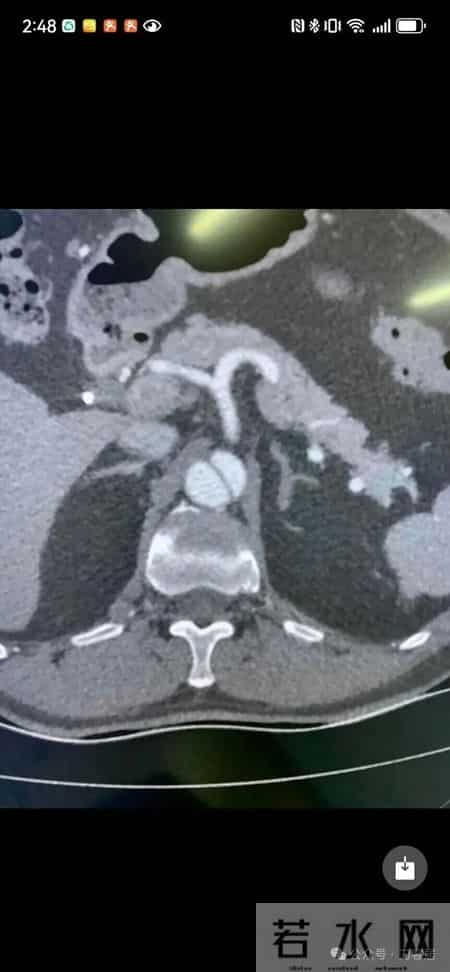

下面是玥佳萱网友所在医院给他提供的一个动脉夹层血管造影图,实际上不是那个猝死病人的图像,是一个比较典型的动脉夹层血管造影图。即使如此,我相信很多骨科医生也不认识: